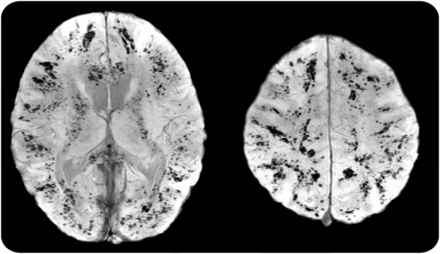

一个8岁的女孩因坏死性耐甲氧西林感染性休克金黄色葡萄球菌(MRSA)肺炎发达终末器官损害的迹象,新右半身不遂,注视偏好。Susceptibility-weighted MRI显示广泛的多焦点的瘀点优先在灰白色物质界面由于感染性微栓塞(图)。出血的机制包括小血管阻塞导致霉菌的动脉瘤的形成与破裂或化脓性动脉炎没有动脉瘤形成。1颅内出血与转移性葡萄球菌感染很少被描述2尤其值得注意和弥漫性脑瘀点设置的转移性耐甲氧西林金黄色葡萄球菌。

图

Susceptibility-weighted MRI脑半球

无数的离散瘀斑的出血在大脑半球在轴向susceptibility-weighted MRI演示的那样。大多数病变位于灰白色接口。